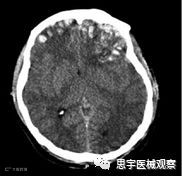

创伤性脑损伤(TBI),也称为脑损伤或头部损伤,是由外伤引起的脑组织损害。TBI会造成认知、感觉加工、运动执行、语言交流以及行为和精神等多方面的损伤,其功能破坏的程度取决于脑损伤的区域和程度。

TBI患者的CT图像